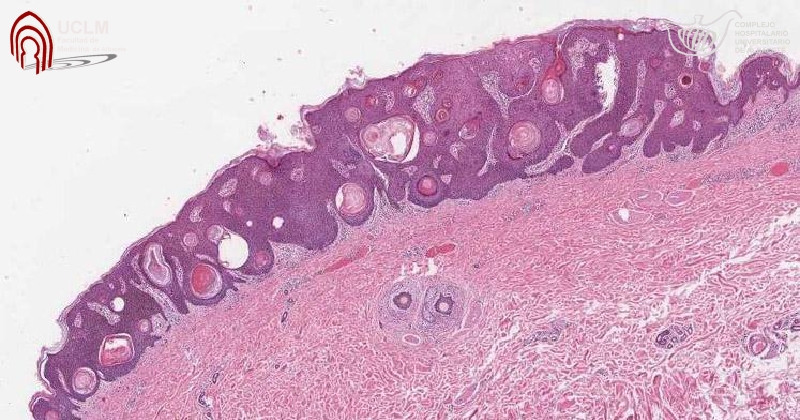

Jama , 8 de enero de 2019 La FDA ha aprobado una solución tópica de peróxido de hidrógeno al 40% (Eskata - Aclaris Therapeutics) para el tratamiento de las queratosis seborreicas elevadas (QS) en adultos. Es el primer fármaco aprobado para esta indicación. (El peróxido de hidrógeno está disponible sin receta para uso tópico como solución al 3%).